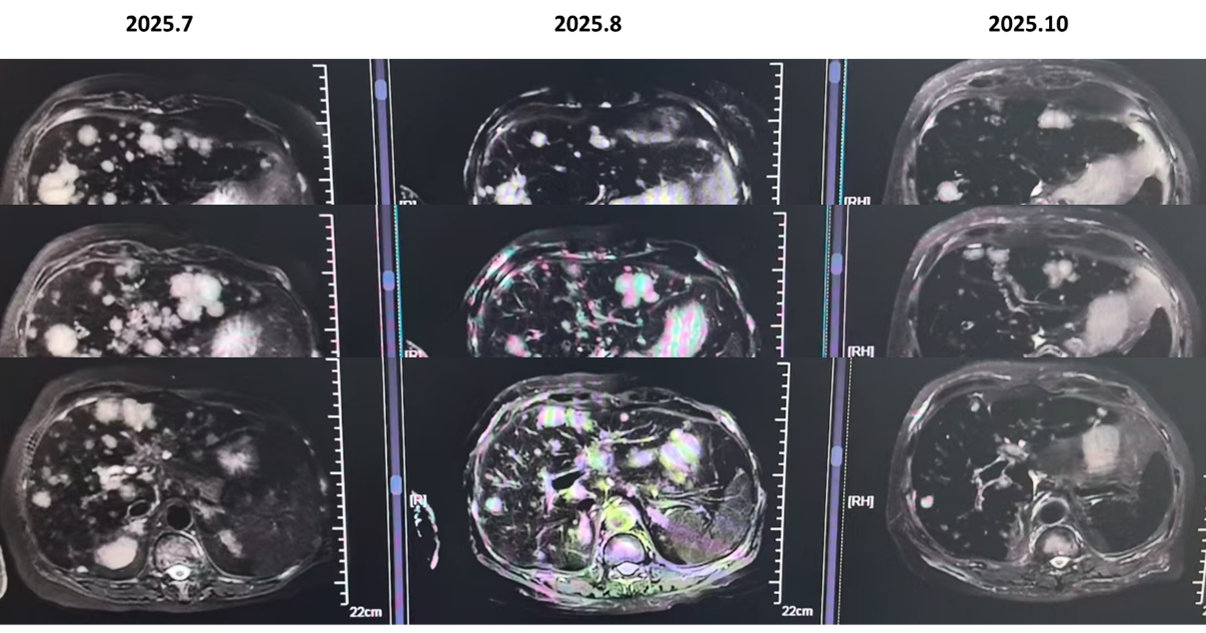

疗效评估: 治疗后复查影像学,患者肝脏病灶显著缩小,评效实现部分缓解。

在INAVO120研究中,伊那利塞三联方案将PIK3CA突变人群的中位无进展生存从7.3个月显著延长至17.2个月,降低了58%的疾病进展风险(风险比:0.42)。即便在该例患者已出现脑转移及多脏器转移的高风险负荷下,四线应用含伊那利塞的方案仍能观察到肝脏病灶的部分缓解,这有力证明:针对PIK3CA这一核心驱动基因精准打击,是打破耐药天花板、实现晚期挽救治疗的关键。